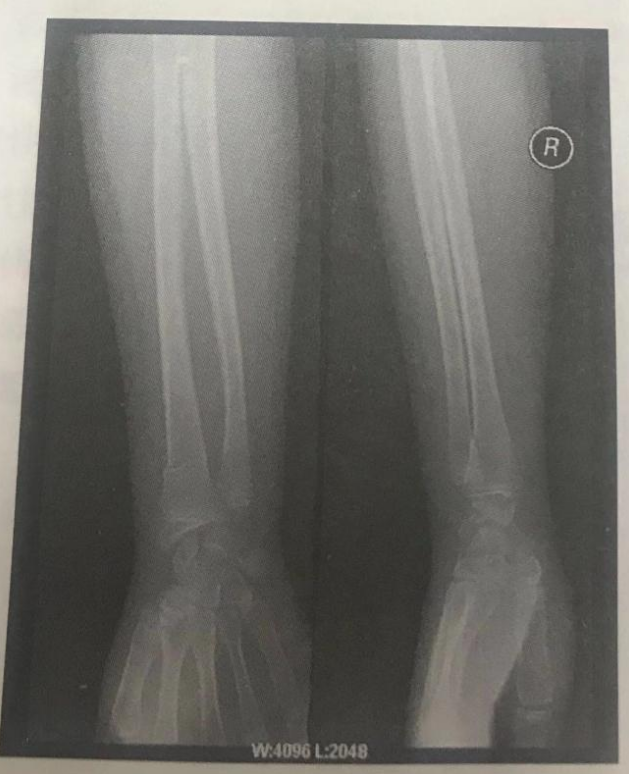

根據(jù)下面X線片判斷臨床意義。(5分)

右撓骨遠端青枝骨折。